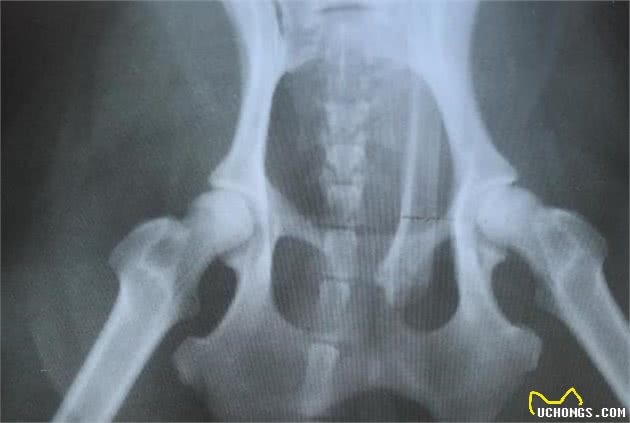

X光片可以检测到腰椎区域的非特异性关节改变,这是常见的,可能没有任何迹象。如果椎间盘破裂,可见椎间盘间隙变窄或紧贴脊髓。

如有必要,医生建议做脊髓造影,可以看到脊髓承受的压力。当然,CT、核磁共振也可以诊断腰椎问题。